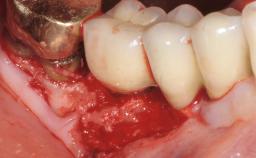

Paolo Casentini demonstrates that peri-implantitis can be successfully treated even at an advanced stage. He discusses a case in which the existing implants and prostheses were both retained while regenerating the defect and creating a band of keratinized tissue. A 69-year-old female patient was referred by her general dentist for evaluation of a recurrent infection at previously placed and restored implants in the posterior left mandible. The patient’s chief complaint was recurrent swelling and pain in the molar region of the left posterior mandible with discomfort during brushing in the same area. The patient reported receiving two implants (36 and 37) nine years earlier.